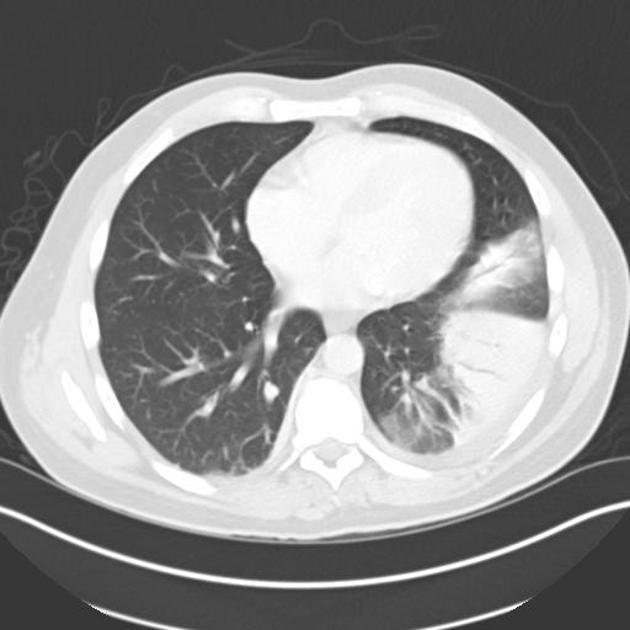

Air space opacification

is a descriptive term that refers to filling of the pulmonary tree with material that attenuates x-rays more than the surrounding lung parenchyma. It is one of the many patterns of lung opacification and is equivalent to the pathological diagnosis of pulmonary consolidation.

In radiological studies ________ _______ presents as increased attenuation of the lung parenchyma causing obscuration of pulmonary vessels, without significant loss of volume, in the segment(s) affected. Air bronchograms can also be found

Lung Consolidation

The opacification is caused by fluid or solid material within the airways that causes a difference in the relative attenuation of the lung: